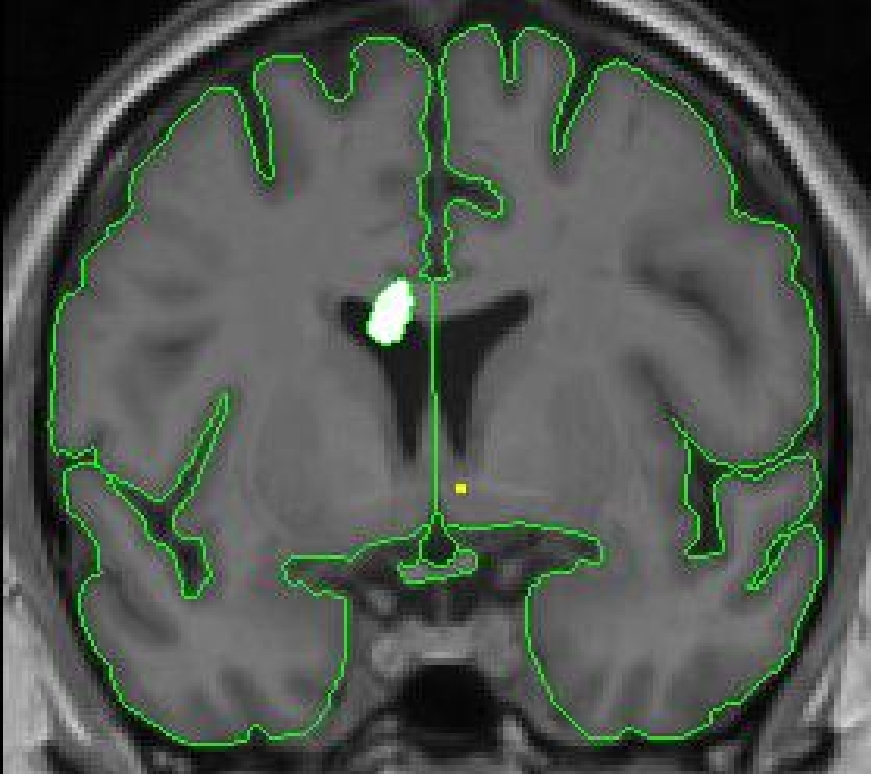

The lateral ventricles are bilateral C-shaped structures that extend through

all four lobes of the brain. They are filled with cerebral spinal fluid (CSF),

and for this reason appear black on the MRI scan. There are five different

parts to each lateral ventricle: the anterior horn (in the frontal lobe),

the body (in the frontal and parietal lobes), the posterior horn (extending

in the occipital lobe), the inferior horn (in the temporal lobes), and the

atrium (where the body, inferior horn, and posterior horn meet).

For the purposes of segmentation, we consider all parts except for the inferior

horn as lateral ventricle. The inferior horn is labeled as "inferior lateral

ventricle" and its method of extraction is described elsewhere.

The lateral ventricles are bordered anteriorly by white matter. As you move posteriorly, the lateral wall of the ventricle is bordered by the caudate, and medially by white matter. Moving posteriorly, the lateral ventricles may appear as if they are connected along the midline. They are actually separated by the septum pellucidum. At this point the bottom wall of the lateral ventricle is bordered by thalamus. As you continue to move posteriorly towards the atrium, the thalamus no longer borders the ventricle; hippocampus becomes the medial border. Caudate still comprises the medial border of the ventricle, but it is difficult to visualize on the MRI scan. As you move past the atrium, the lateral ventricle is surrounded by white matter.